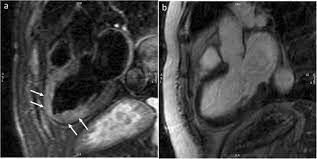

Left Ventricular Function Recovery In Peripartum Cardiomyopathy A Cardiovascular Magnetic Resonance Study By Myocardial T1 And T2 Mapping Journal Of Cardiovascular Magnetic Resonance Full Text

Left Ventricular Function Recovery In Peripartum Cardiomyopathy A Cardiovascular Magnetic Resonance Study By Myocardial T1 And T2 Mapping Journal Of Cardiovascular Magnetic Resonance Full Text from media.springernature.com

In the case of fulminant. Journal of the american college of cardiology vol. • it can be acute, subacute, or chronic, and. More specifically, it is described as. Management, and therapy of myocarditis: Symptoms can include shortness of breath, chest pain, decreased ability to exercise, and an irregular heartbeat. 17 march 2005 suspected myocarditis in sri lanka. Myocarditis can affect your heart muscle and your heart's electrical system, reducing your heart's ability to pump.

Patients of suspected myocarditis are clinically evaluated to distinguish fulminant lymphocytic myocarditis from acute lymphocytic myocarditis. Most of the time, it is caused by an infection that reaches the heart. Cardiomyopathies, myocarditis, and pericardial disease. Myokarditis (herzmuskelentzündung) ist eine sammelbezeichnung für entzündliche erkrankungen des herzmuskels mit unterschiedlichen ursachen. Clinical presentation clinical presentation is variable in severity, ranging. Myocarditis is an inflammation of the heart muscle (myocardium). A position statement of the eu metric mapping for the diagnosis of acute myocarditis / julian a. Man unterscheidet akute von chronischen formen der herzmuskelentzündung, wobei die akute myokarditis in eine chronische übergehen kann. Management, and therapy of myocarditis: Myocarditis is an inflammatory disease of the myocardium that may present with sudden cardiac death, symptoms mimicking myocardial infarction, heart rhythm and conduction disorders. Sie kann akut oder chronisch verlaufen. In the case of fulminant. More specifically, it is described as.